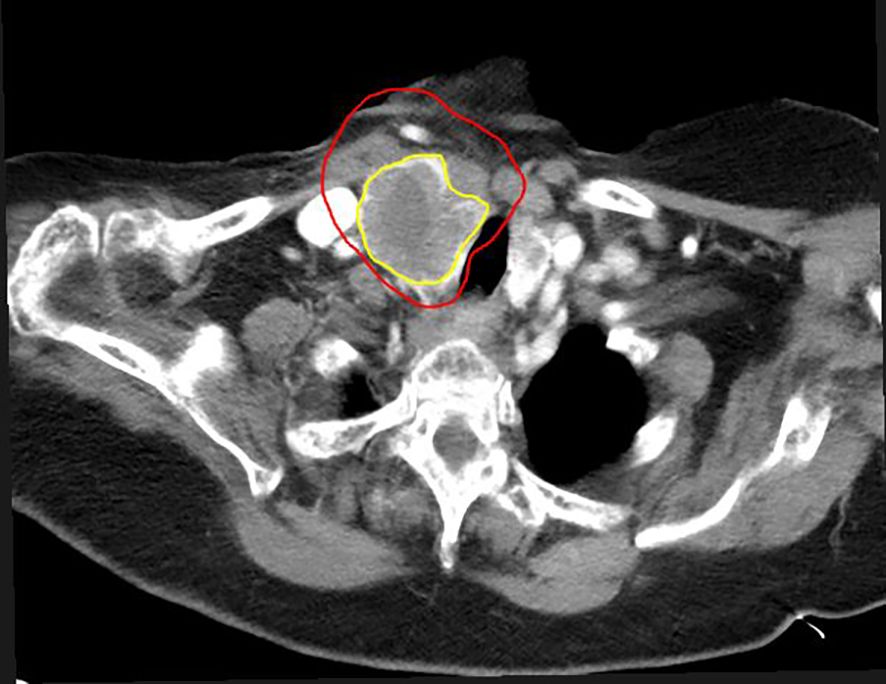

Early Experience with SBRT-based Partial Tumor irradiation targeting Hypoxic segment (SBRT-PATHY) of large bulky tumors.

Large bulky tumors possess poor prognostic characteristics that make tumor control difficult. SBRT-based Partial Tumor irradiation targeting Hypoxic segment (SBRT-PATHY) has been described as a spatially fractionated radiotherapy technique that induces both bystander and abscopal effects by sparing the peri-tumoral immune micro-environment thus minimizing the negative effects of radiation induced lymphopenia. The aim of these case reports is to present our early experience of 4 cases in the utilization of SBRT-PATHY at our institution.